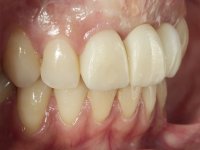

Na fase inicial, foi proposto à paciente fazer a exposição cirúrgica do implante e após avaliação clínica tomar decisões protéticas. Colocado o parafuso de cicatrização e feita a cicatrização dos tecidos moles, foi constatada uma posição inadequada do implante. Perante o dramatismo da situação foi proposto à paciente a remoção do implante e após regeneração tecidular colocar um novo implante. Esta proposta foi recusada pela paciente e foi sugerido por esta a reabilitação provisória do implante. Nesse sentido foi então feita nova proposta, desta feita, reabilitando o implante. Foi sugerido a confeção de um coto aparafusado e sobre este a colocação de uma coroa de acrílico com componente coronário e gengival. Passados 6 anos com o tratamento provisório a paciente surge na consulta com um abcesso no dente 1.1. Feita a análise clínica e imagiológica decidiu-se extrair os dentes 1.1 e 2.2, submergir o implante, colocar dois implantes no local dos 1.1 e 2.2 e fazer regeneração tecidular adequada. A temporização seria feita com uma ponte provisória de 3 elementos aderida com uma rede aos dentes vizinhos. Após osteointegração seria reabilitada definitivamente com uma ponte de 3 elementos, com infraestrutura de Zr revestida a cerâmica.

A exposição cirúrgica do implante e a colocação do parafuso de cicatrização mostrou-se uma surpresa negativa no que diz respeito à sua posição. Rejeitada a proposta de remoção do implante, avançamos para a sua reabilitação provisória. Foi feita a impressão por técnica de moldeira aberta e em laboratório foi confecionado um coto aparafusado com componente gengival e coronário e uma coroa em acrílico também com estes dois componentes. A coroa provisória foi colocada em boca até ser tomada uma decisão definitiva. Passaram 6 anos até que a paciente retorna à consulta com um abcesso no dente 1.1. Tomada a decisão de extrair os dentes 1.1 e 2.2 foi feita uma impressão para confecionar uma ponte provisória de 3 elementos com uma rede para ser aderida aos dentes adjacentes. A cirurgia foi planificada e realizada, colocando-se os dois implantes no local do 1.1 e 2.2 e o implante no local do 2.1 foi cortado com o objetivo de o submergir, simultaneamente foi feita a regeneração tecidular adequada (Trabalho Cirúrgico realizado por Dr. Manuel Neves). Durante a osteointegração a paciente utilizou a ponte provisória fixa. Foi realizada primeira impressão para a confeção de uma ponte provisória aparafusada em Zr que trabalhou durante 12 semanas os tecidos moles. A impressão definitiva foi feita com a individualização dos transferes. A reabilitação definitiva foi feita com cotos ceramizados e com uma ponte de infraestrutura em Zr revestida por cerâmica. Em virtude da inclinação do implante colocado no local do dente 1.1 a ponte exigiu fixação cimentada.